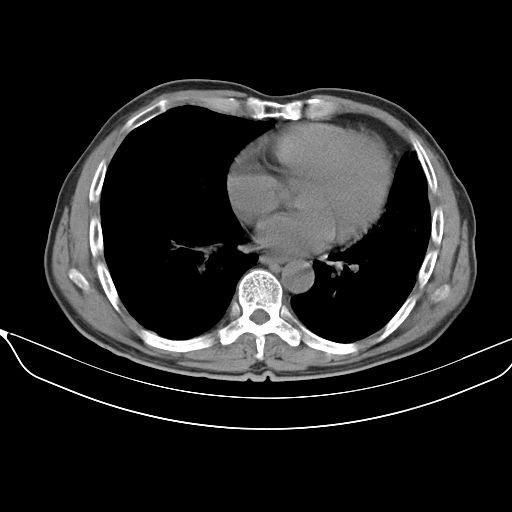

以下是引用心路寻觅在2010-3-1 10:23:00的发言:[br]1、考虑左肺上叶周围型肺癌[br]2、右上肺陈旧性病灶。[br][br][本贴已被 心路寻觅 于 2010-3-1 10:40:18 修改过]

以下是引用shuiyuan在2010-3-1 10:45:00的发言:[br]考虑左肺上叶中心型肺癌伴阻塞型炎症,邻近胸膜受侵。